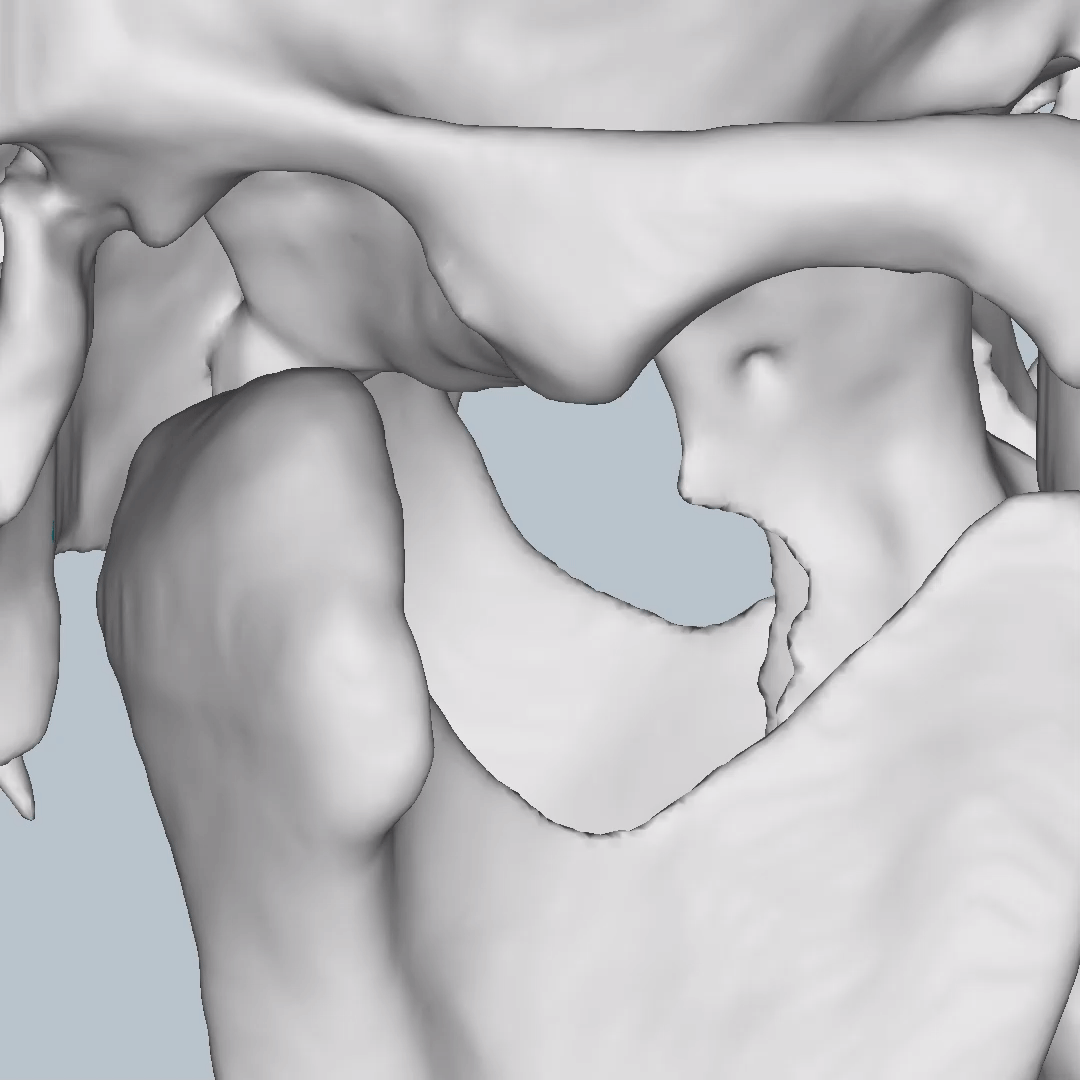

This is one feature that actually made Diagnocat very popular early on. It was the only software that made CBCT segmentation easy. Nowadays, there are several different companies and software that carry out segmentation. Diagnocat was the first and is still arguably the best at it.

So what is Segmentation? It basically means taking the CBCT and delineating all the different 3D structures, bones, individual teeth, etc.

These can then be individually exported via the software by generating STL files from CBCT dicom data. This can be used in other dental software. Jaw STLs can be used in Modjaw (jaw motion capture) for TMJ analysis, for example. As well as in exocad to help visualize the jaws for surgical planning or guide creation.

Being able to take a DICOM file and turn it into STLs is useful for a host of different CAD/CAM indications.

- CBCT segmentation

STLs of upper and lower jaws imported into Modjaw for TMJ analysis in jaw motion. this is made possible by CBCT segmentation using Diagnocat.

The surgical crown lengthening guide was made with the aid of maxilla STL to visualize crestal bone level. Again thanks to CBCT segmentation by Diagnocat.

CBCT Segmentation into STL

Generate STL files from CBCT DICOM data.

Generate maxilla and mandible in one STL file or face, teeth, maxilla, mandible, airway, cranial base, canals as separate STL files.